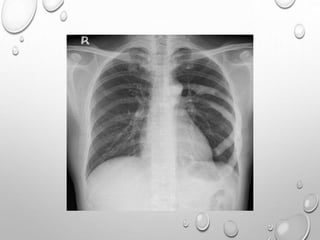

Chest radiograph in an infant demonstrates

overall increased density of osseous

structures due to accumulation of immature

Generalized increased density of bones &

alternating areas of increased & decreased

density in metaphyses (bone-within-bone

appearance).